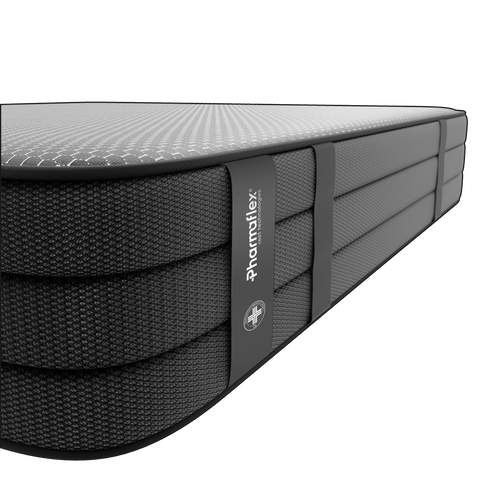

Nasce la nuova Tecnologia per la Decompressione Vertebrale:

Analisi punti di pressione

Questa procedura misura come il peso del corpo viene distribuito sulla superficie di riposo. Durante l'analisi, un individuo si sdraia sul prodotto, e con l'ausilio di tecnologie avanzate si rilevano le zone dove il corpo esercita maggior pressione. Questo permette di identificare aree a rischio di stress o disagio, come le spalle, i fianchi o la zona lombare.

Allineamento vertebrale

Attraverso strumenti all'avanguardia ci impegniamo a monitorare il corretto allineamento del rachide cervicale in ogni posizione di riposo. Lo scopo è di assicurarci che non si verifichino condizioni che possano portare ad uno scompenso muscolare o scheletrico.

Decompressione vertebrale

Questo test avanzato ad alta precisione ha lo scopo di monitorare la colonna vertebrale prima e dopo l'utilizzo dei nostri prodotti. Confrontando i risultati rispetto ad altri prodotti, i nostri ingegneri biomedici possono valutare con precisione quanto efficacemente l'azione dei dispositivi abbia alleviato la compressione sui dischi e le vertebre.

Rilassamento muscolare

In questa fase elettrodi sottili vengono attaccati alla pelle o inseriti nei muscoli per registrare i segnali elettrici generati durante le contrazioni muscolari. Questo test è particolarmente importante in quanto ci consente di rilevare l'effettiva capacità di nostri prodotti di ridurre la tensione muscolare e valutare la qualità del riposo.